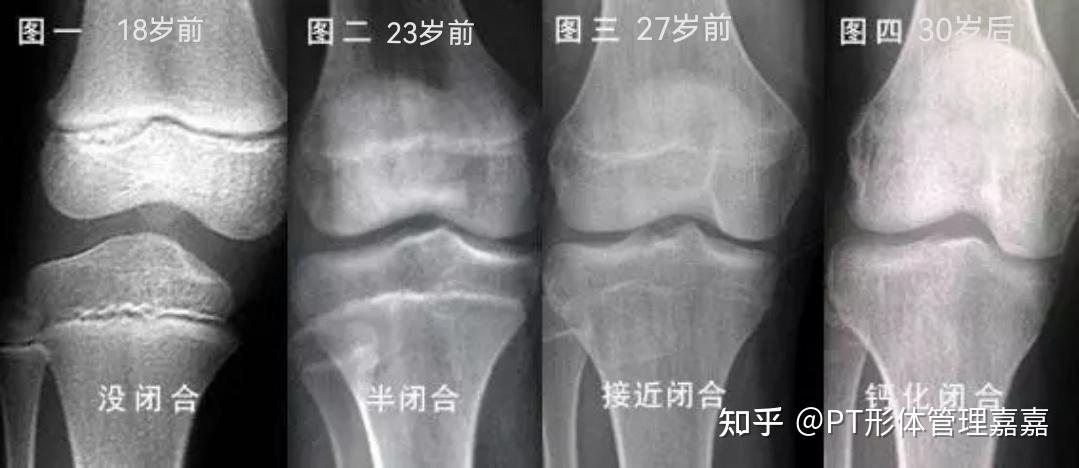

212岁的孩子生长公式是年龄*7+75,青春期的时候男孩子可以长2530cm,女孩子可以长2025cm每人每年的生长速度不能低于5cm,是在骨骺线愈合以前2223岁骨骺线愈合就不能生长,如果30岁时还要求长个,一般不大可能因为这时骨骺线已经愈合,就是使用生长激素也容易产生肢端肥大症,而不能造成躯干。

30岁人群一般很难再长高,但在特殊情况下可能通过干预增加身高,更多是通过改善体态和生活方式优化视觉身高骨骺线闭合是关键因素30岁人群的骨骺线通常已完全闭合,骨骼生长板停止活动,自然长高的生理基础基本消失若骨骺线未闭合如因内分泌疾病导致发育延迟,需在医生指导下通过生长激素治疗营养支。